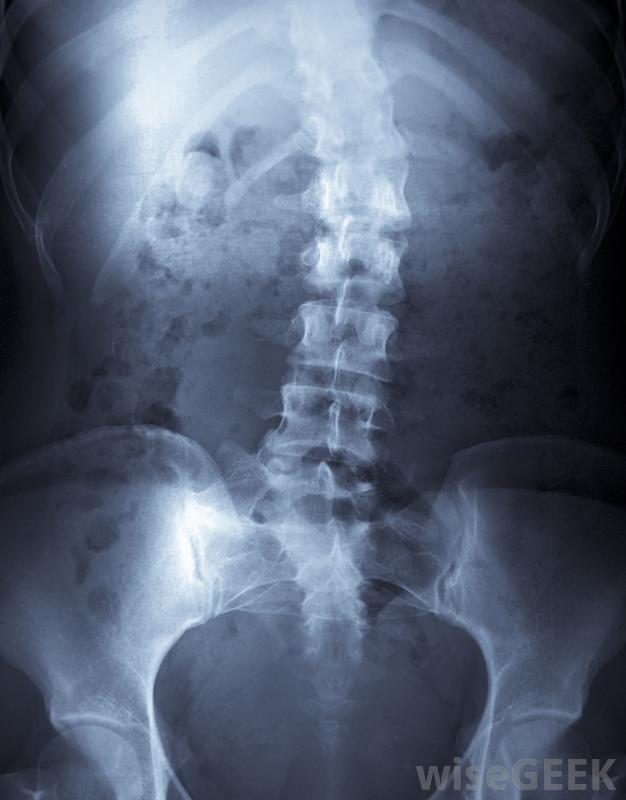

手术后患者可能会遇到许多脊柱融合并发症,包括神经损伤、慢性背痛和感染。脊柱融合是一项复杂的医疗过程,需要将椎骨融合在一起。愈合过程可能需要长达一年的时间,并发症的风险比其他医疗程序高。尽管医疗进步和更好的病人护理已经降低了主要并发症的可能性,脊柱侧凸是脊柱异常弯曲的一种治疗方法脊柱融合术是两个或两个以上的椎骨融合在一起的一种医疗程序。这可能有很多原因,但最常见的是脊柱侧凸的矫正,外科医生将脊柱伸直,将尸体骨插入椎骨之间,尸体骨起到桥梁的作用,使脊椎融合在一起,一旦愈合,脊柱将保持挺直,融合的骨头阻止了脊柱侧弯的进一步发展

脊柱融合是两个或多个椎骨融合在一起的医疗过程脊柱融合并发症包括手术引起的不同程度的神经损伤。由于脊柱融合涉及整个背部,手术可以切断许多周围神经在康复过程中,随着神经的愈合,患者可能会出现各种症状;失去感觉或对触觉过敏的情况并不少见。许多月或数年的时间可能会让患者体验到更多正常的感觉。即使如此,触觉的减弱可能会在患者的余生中持续存在

接受脊柱融合术的患者可能会出现神经损伤、慢性背痛或感染,具体取决于位置和程度在脊柱融合术中,慢性背痛可能成为患者脊柱融合术并发症的一部分。例如,矫正脊柱侧凸的脊柱融合术涉及到大量肌肉组织的切割。即使在肌肉完全愈合后,患者也可能比手术前出现更多的背痛脊柱融合术的另一个并发症是术后感染。抗抗生素的细菌如MRSA对所有住院病人都有风险。那些免疫系统受到抑制或从任何类型的手术中恢复过来的患者风险更大是非常危险的,并且会使脊柱融合的恢复变得非常复杂。历史上,最常见的脊柱融合并发症包括不正确或失败的融合。从20世纪初开始,术后病人将被固定在石膏内长达一年20世纪50年代,Harrington棒的引入降低了并发症的总体几率,尽管患者仍需花费数月时间进行一系列的石膏和支架治疗。Harrington棒技术的进步已经消除了对术后支架的需求。今天,患者的融合不太可能失败或设置不正确。